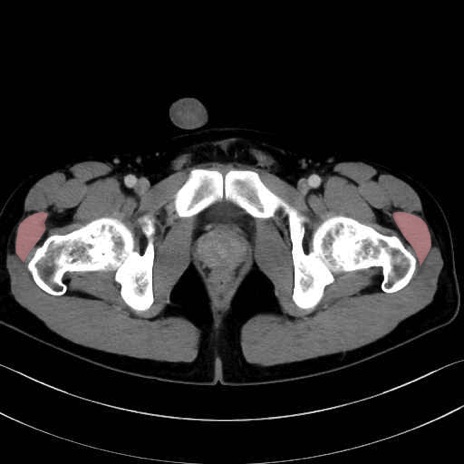

中殿筋 (Gluteus medius)

小殿筋 (Gluteus minimus)

大腿筋膜張筋 (Tensor fasciae latae)